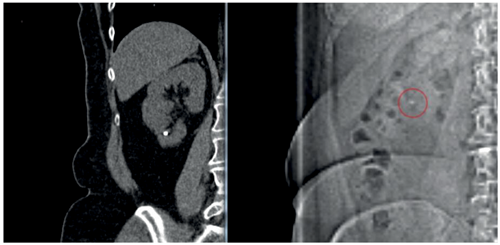

Figure 2. Stone visible on scout film - for intraoperative targeting and follow-up.

‘Percussion, diuresis and inversion’ (PDI), may be suggested to aid the passage of the lower pole stone fragments. In the Donaldson study [13], RIRS had a greater likelihood of achieving stone-free over SWL (risk ratio 1.31; 95% CI, 1.08-1.59), but this can be reduced with auxiliary manoeuvres such as PDI therapy [25].

Stone-free rates are suggested to range from 40-60% [26], depending on the methods used. Diuresis can be stimulated by a 500ml bolus of water or 20mg of furosemide, whilst inversion (of 45 degrees) and percussion are usually performed in the comfort of the patient’s home surroundings (Figure 3). Not surprisingly, this cannot always be feasible and therefore a suggested modified approach includes swimming after ingestion of 500ml of water.